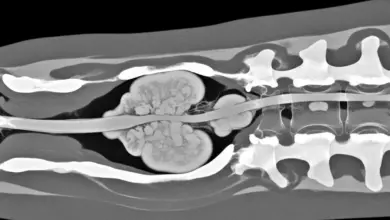

Dor nas costas pode ser tumor? Sinais e exames

Muitos pacientes chegam ao consultório preocupados se dor nas costas pode ser tumor, mas é importante deixar claro que essa…